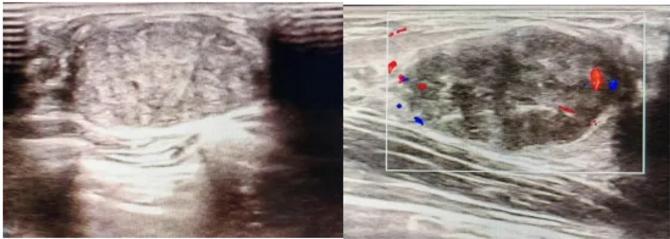

三、彩超檢查:無創(chuàng)檢查的“黃金眼”

高分辨率:可清晰顯示腫塊形態(tài)、血流信號,敏感度達80%-90%。

2.彩超報告關(guān)鍵指標

形態(tài):良性多呈橢圓形或分葉狀,邊界光滑。

縱橫比: 良性通常<1(橫徑>縱徑) 。

血流信號:纖維瘤血流較少,惡性常伴豐富雜亂血流。

鈣化:粗大鈣化多為良性,細小簇狀鈣化需警惕惡性。

BI-RADS分級:2-3類提示良性,4類以上需進一步檢查。

典型表現(xiàn):

橢圓形低回聲團塊,包膜完整,內(nèi)部回聲均勻,后方回聲增強,周邊無“蟹足樣”浸潤。